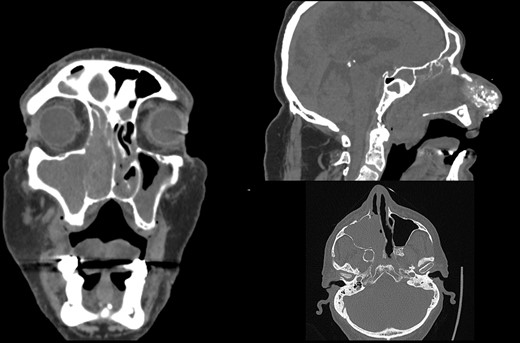

A 66-year-old patient with a history of heart disease presented to our hospital with recurrent epistaxis, hyposmia and nasal congestion. On examination, the patient was found with an ulcer-proliferative mass that obstructed the entire right nasal cavity spreading from the epipharynx to the oropharynx. No lymphadenopathy was detectable. Computerized tomography (CT) scan of the head and neck region showed expansive mass primarily in the right maxillary sinus spreading throughout the ostiomeatal complex, infiltrating the septum, all ethmoid cells, entering into the frontal sinus through frontoethmoidal recess and penetrating the nasopharynx. The soft palate was suppressed by the described mass and the initial infiltration of the right pterygoid muscles was also visible (Fig. 1). A biopsy revealed tumor cells built up of a dense mass of small blue cells with round and hyperchromatic nuclei with mitosis. Tumor cells had an ill-defined border and grew into syncytia. Desmoplasia was abundant, with areas of osteoid or chondro-osteoid-like material deposition. Immunohistochemically tumor cells were positive for vimentin, CD99, ERG, FLI-1, MDM2, CDK4, CD56, CK 5/6 and histochemically showed PAS-positive glycogen in the cytoplasm. A working diagnosis leaded to highly malignant and poorly differentiated sarcoma with elements of Ewing’s sarcoma and elements of bone differentiated tumor. Before proceeding with wide surgical resection, the patient received seven cycles of neoadjuvant chemotherapy with paclitaxel and carboplatin. The aggressive tumor growth was stopped, but tumor mass was minimally reduced. Surgical resection of the tumor was performed by mid-face degloving approach with temporary ostectomy of the frontal process of the maxilla and the anterior wall of the maxillary sinus. Medial maxillectomy and resection of the tumor were then performed. The tumor extended from the lateral wall of the maxillary sinus to the anterior part of the inferior nasal turbinate up to 5 cm below the epipharynx into the oropharynx. The posterior part of the septum on the rostrum was removed and bilateral ethmoidectomy was performed. The lamina papyracea was also resected; the skull base was inspected and was completely free of tumor. The part of the nasolacrimal canal that was in contact with the tumor was resected and a small stump was left on the lacrimal sac on which marsupialization was performed. Surrounding margins were free of tumor cells on the intraoperative frozen section (Fig. 2).

Initial CT scan of the head and neck region in coronal, axial and sagittal view show expansive formation predominantly in the right half of the paranasal sinuses. Right maxillary sinus is completely filled with tumor mass as well as right nasal cavity with infiltration of the septum, all ethmoid cells and the frontal sinus through frontoethmoid recess. Sagittal view show tumor spread in the nasopharynx.